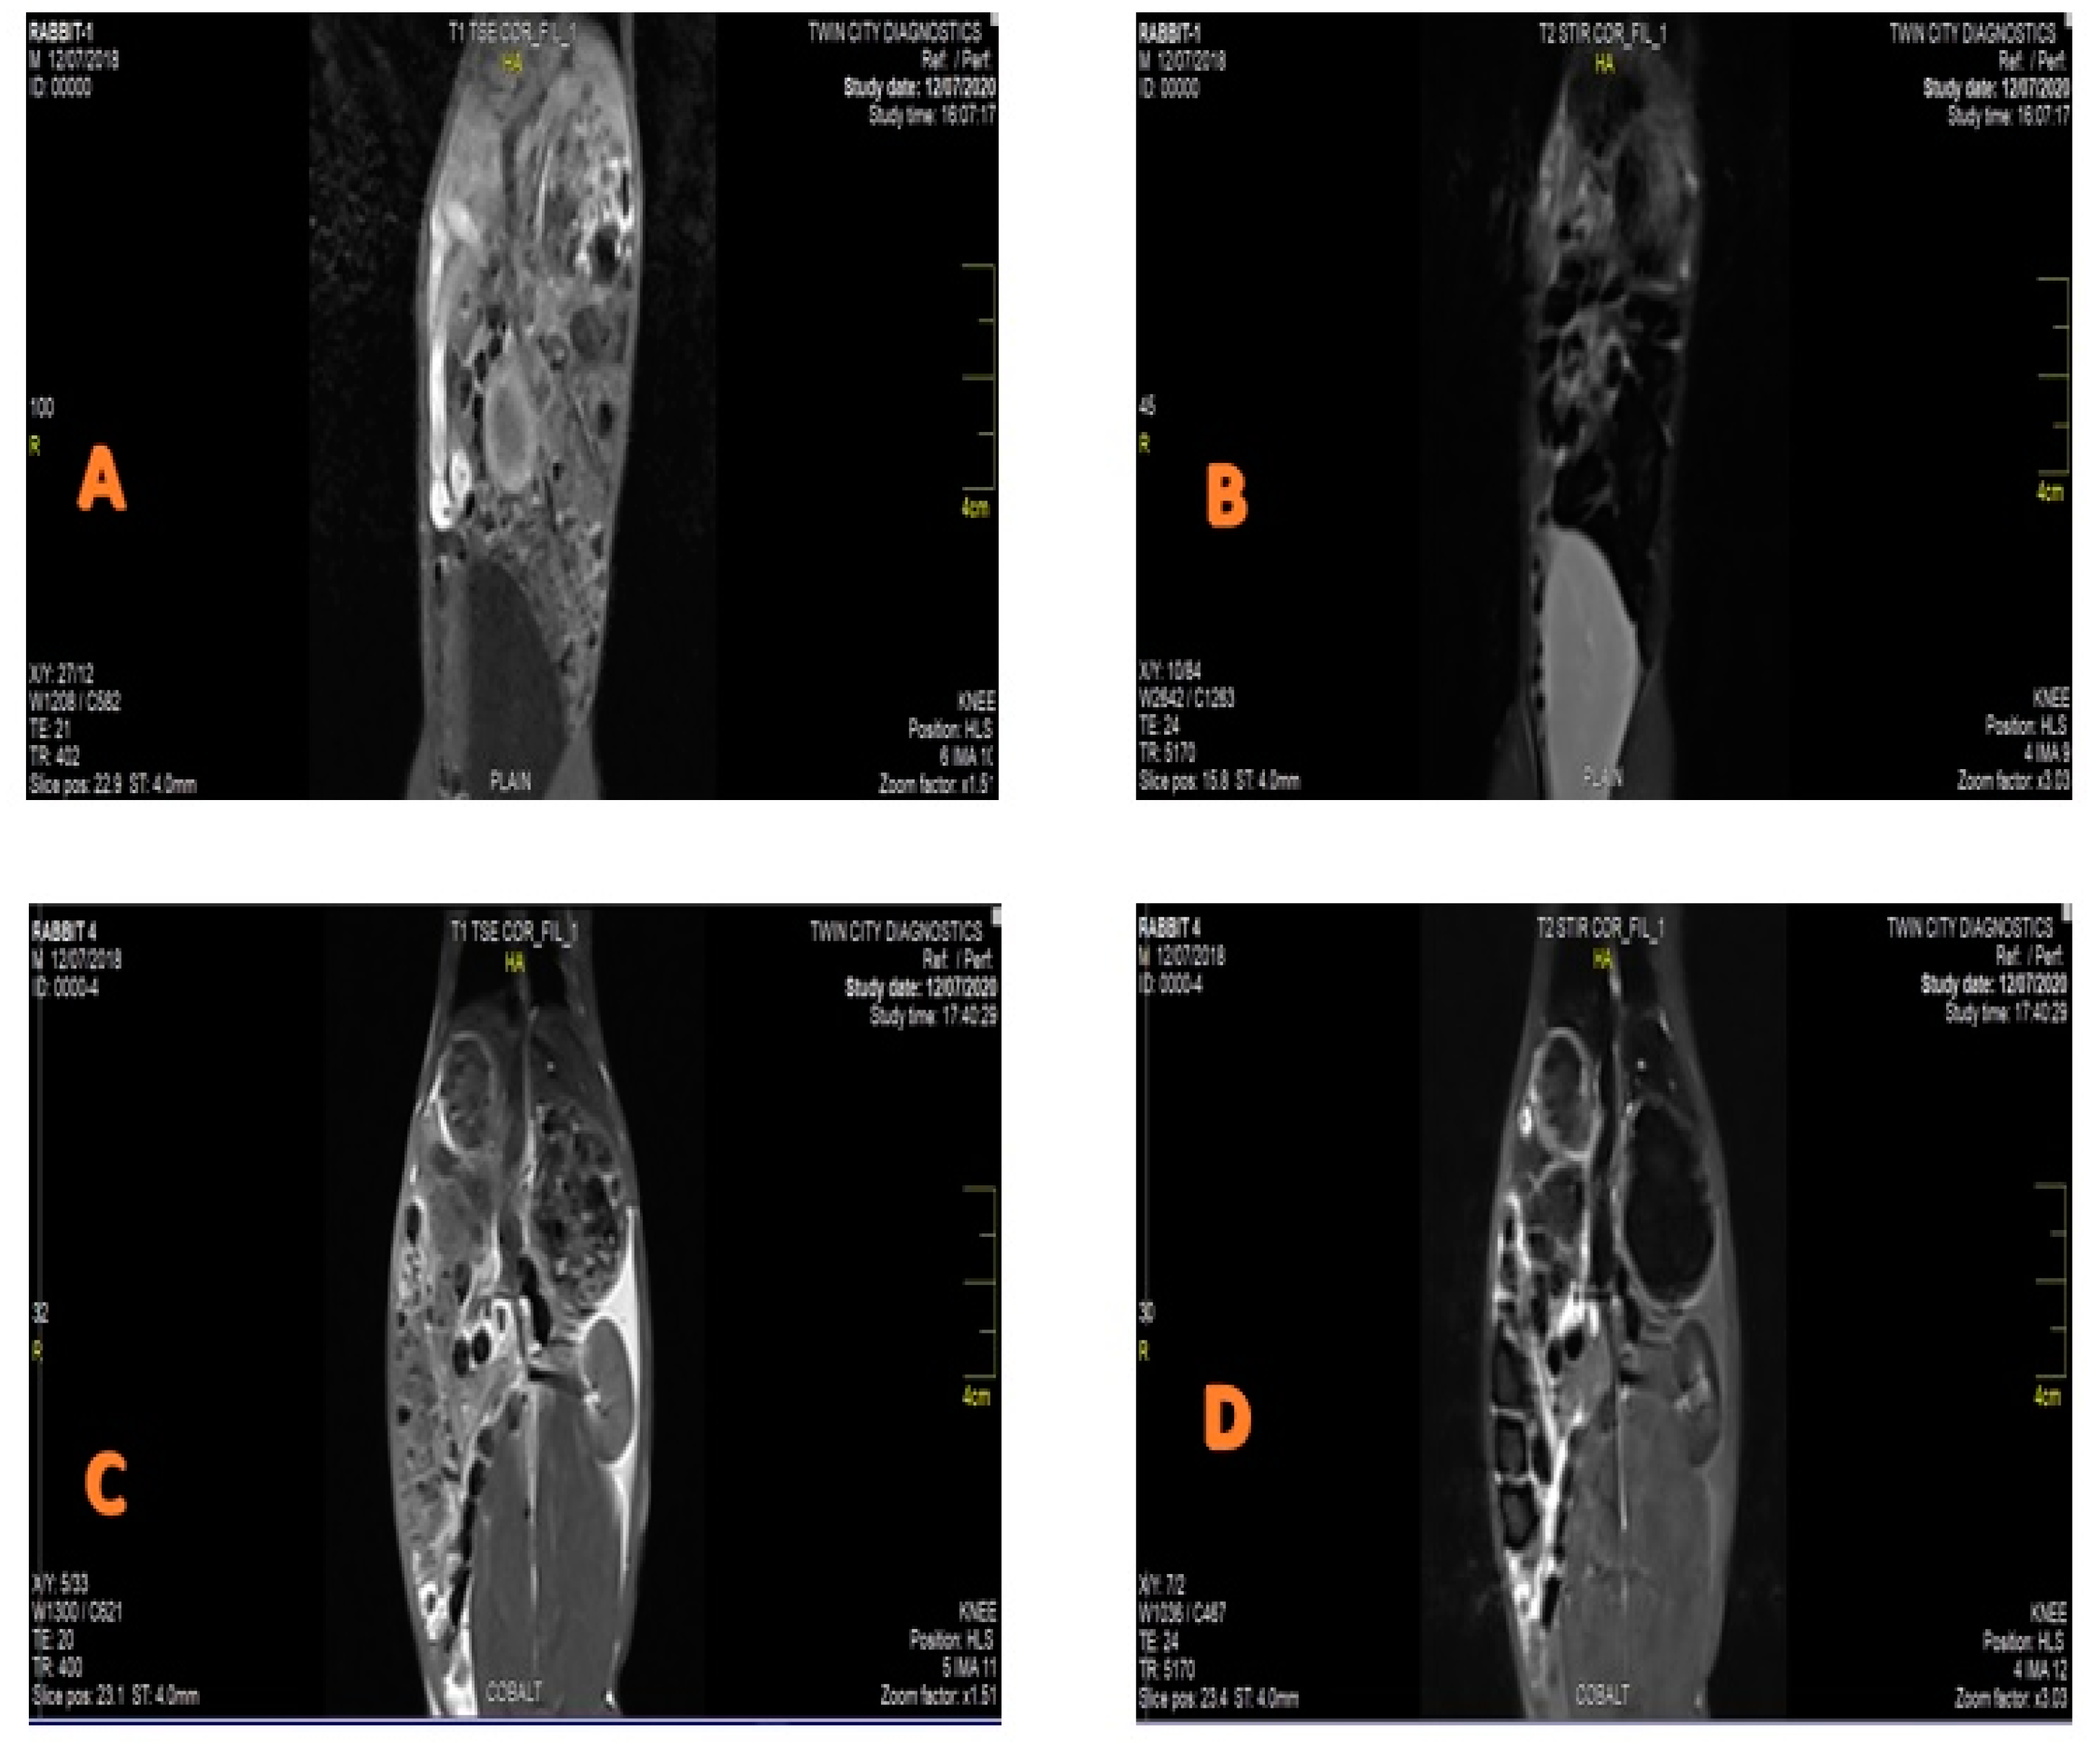

3.2. MRI Contrast Agent and Relaxivity

CIONPs are presumed to be a promising candidate for the development of a T2 contrast agent with better relaxivity. CIONPs essentially disrupted the magnetic relaxation process of protons in the tissue, causing the proton’s spin–spin relaxation time to shorten. The relatively high magnetization caused the relaxivity of the body’s underwent tissue to improve. In this investigation, MRI was performed at a low-field MRI magnetron (0.35 T) in order to obtain high contrast in the organs, such as the rabbit’s liver and spleen. An intravenous dose of the contrast agent was administered in the ear vein. We evaluated the intensity of the signal experienced by the contrast agent as with CIONPs, using IQ View software (for liver, I = 1427 S.D = 121.1, spleen I = 1702 S.D = 221.3), as shown in Figure 3 and Figure 4. The slope of the line fitted to the 1/T2 versus concentration plot was used to calculate proton relaxivity (r2) (d). CIONPs had a r2 value of 112.4 mM−1 S−1. The 1/T1 value was shown as a function of the varied concentrations plot (Figure 4C) to confirm that CIONPs exhibited a negative T2-type of contrast. When compared to r2, the r1 relaxivity is minimal.

In vivo, MRI results exhibited a strong contrast of the liver and stomach, indicating that CIONPs may play a significant role, even at low-field MRI units, in diagnostic modality to identify diseases of organs in the body. Contrast agent choice is based on the relaxivity ratio r2/r1, which can be enhanced depending on the size, charge concentration, and field strength [24,64,65,66]. T1 relaxation seems to be a little faster in the liver than in the spleen based on relaxivity, and T2 relaxation also appears to be slightly faster in the liver than in the spleen [39]. Earlier research, however, has found different relaxation rates in the liver and spleens of rats and rabbits. Consequently, the proposed CIONPs could be used as negative contrast agents in diagnostic imaging to reveal organ pathology even with limited-field MRI equipment. According to earlier studies [67,68,69], CIONPs with many of these properties are good for in vivo biomedical fields such as the MRI contrast agent and relaxivity.

Figure 3. MRI Images of spleen and liver of the (A,B) control/untreated rabbits presenting no contrast; (C,D) treated rabbits presenting contrast after exposure of CoFe2O4 nanoparticles.